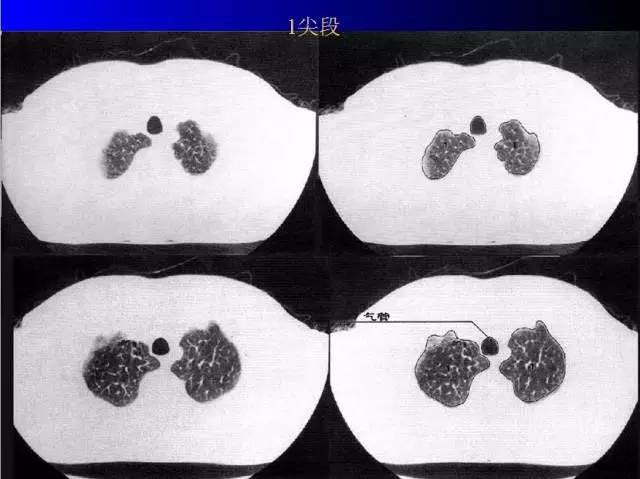

肺部基础X片及CT片解读